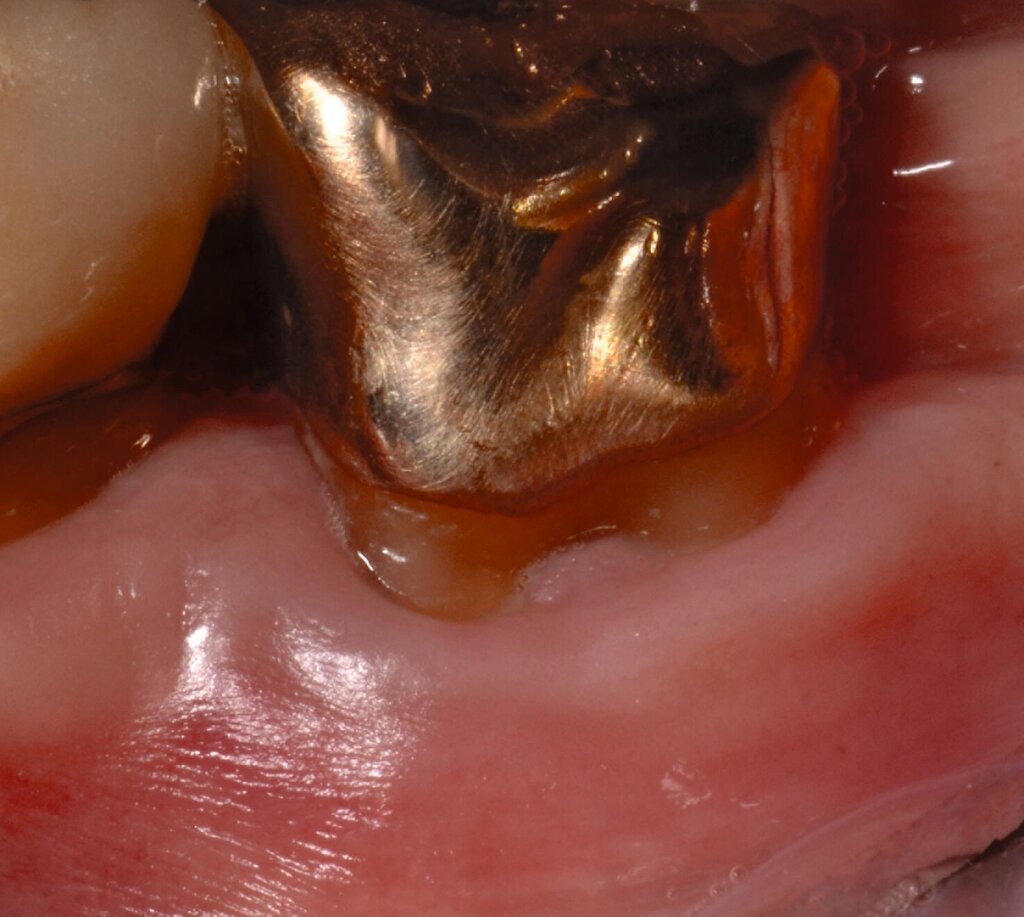

3. Regenerative Parodontalchirurgie

Ziel ist es, einen ausreichenden Zugang zum Defekt für eine sorgfältige Instrumentierung und die Applikation des Biomaterials zu erhalten. Bei isolierten Defekten können vertikale Entlastungsinzisionen verwendet werden. Alternativ kann der Lappen nach lateral zu den benachbarten Zähnen erweitert werden. Keratinisiertes Gewebe sollte durch intrasulkuläre Inzision und die Anhebung eines Mukoperiostlappens erhalten werden. Das Granulationsgewebe wird entfernt und die freiliegenden Wurzeloberflächen werden sorgfältig mit Handinstrumenten, oszillierenden Scalern (optional mit fein diamantierten Spitzen) oder rotierenden Instrumenten gereinigt. Wurzelanomalien wie Schmelzvorsprünge/-perlen sollten entfernt werden. Wenn EMD Teil der Regenerationsstrategie ist, wird es in der Regel nach einer zweiminütigen Wurzelkonditionierung mit Ethylendiamintetraacetat (EDTA) und Spülung mit steriler Kochsalzlösung angewendet. Anschließend kann ein Knochentransplantat/-ersatzmaterial verwendet werden, um den Furkationsdefekt aufzufüllen.

Alternativ kann eine GTR-Barrieremembran mit oder ohne zusätzlichen Defektfüller appliziert werden. Die Barrieremembran wird mit einer resorbierbaren Umschlingungsnaht befestigt, um den Furkationseingang abzudecken und die Wund- und Koagulumstabilisierung zu fördern. Um eine vollständige Abdeckung der Barriere zu ermöglichen, kann das Periost durchtrennt werden, um den Lappen leicht koronal zu verschieben. Der Lappen wird mit einer Umschlingungsnaht und Einzelknopfnähten über den vertikalen Entlastungsinzisionen oder mit interdentalen Nähten im Fall eines lateral extendierten Lappens in einer koronalen Position gesichert. Der Patient wird angewiesen, für einen Zeitraum von bis zu vier Wochen auf die mechanische Plaqueentfernung im Operationsgebiet zu verzichten. Während dieser Zeit werden Chlorhexidin-Spülungen oder -Gel verwendet. Der Patient kehrt zur Kontrolle der Wundheilung nach ein und zwei Wochen zurück, wenn die Nähte entfernt werden. Die Interdentalhygiene und die mechanische Plaqueentfernung werden nach vier Wochen wieder aufgenommen. Zudem wird ein individuelles Recallprogramm zur unterstützenden Parodontitistherapie (UPT) festgelegt.